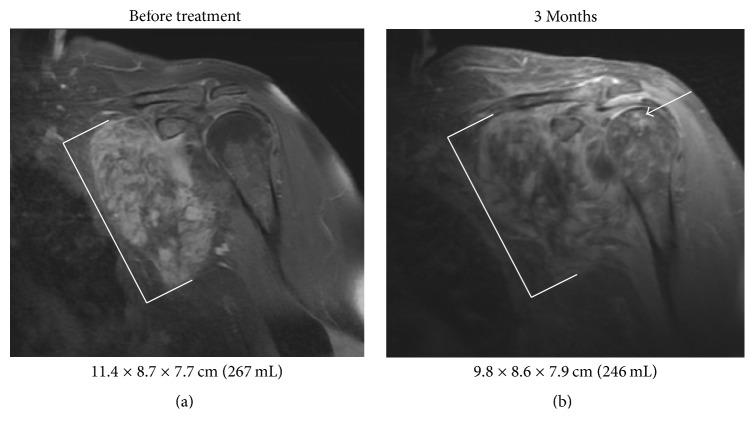

Desmoid tumors are locally aggressive fibroproliferative neoplasms that can lead to pain and dysfunction due to compression of nerves and surrounding structures. Desmoid tumors often progress through medical therapy, and there is frequently a delay of multiple months before radiation can provide symptomatic relief. To achieve more rapid symptomatic relief and tumor regression for unresectable desmoid tumors causing significant morbidity such as brachial plexus impingement with loss of extremity function, we have selectively utilized a combination of imatinib and radiation therapy. Here, we retrospectively review four patients treated with concurrent imatinib and radiation therapy. The treatment was typically tolerated with minimal toxicity though one patient developed avascular necrosis of the irradiated humeral head possibly related to the combined treatment. All the patients treated have had a partial response or stable disease on imaging. Improvement of symptoms was observed in all the treated patients with a median time to relief of 2.5 months after starting radiation therapy. Concurrent radiation and imatinib may represent a viable treatment option for unresectable and symptomatic desmoid tumors where rapid relief is needed to prevent permanent loss of function.

摘要

硬纤维瘤是局部侵袭性纤维增生性肿瘤,可因压迫神经和周围结构而导致疼痛和功能障碍。硬纤维瘤常通过药物治疗进展,在放疗能提供症状缓解之前,通常会有几个月的延迟。为了使导致严重发病(如臂丛神经受压伴肢体功能丧失)的不可切除硬纤维瘤更快地获得症状缓解和肿瘤消退,我们选择性地使用了伊马替尼和放疗的联合治疗。在此,我们回顾性分析了4例接受伊马替尼和放疗联合治疗的患者。该治疗通常耐受性良好,毒性极小,不过有1例患者发生了照射肱骨头的缺血性坏死,可能与联合治疗有关。所有接受治疗的患者在影像学上均有部分缓解或病情稳定。所有接受治疗的患者症状均有改善,开始放疗后症状缓解的中位时间为2.5个月。对于需要快速缓解以防止永久性功能丧失的不可切除且有症状的硬纤维瘤,放疗与伊马替尼联合治疗可能是一种可行的治疗选择。